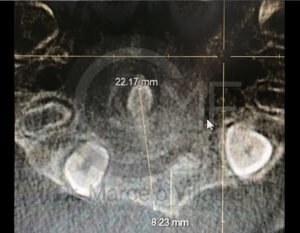

Antes de la extracción se realiza una valoración clínica y estudios de imagen, como radiografías panorámicas o tomografías, para conocer la posición del tercer molar, su relación con los nervios y planificar un procedimiento seguro y adecuado para cada paciente.

No es recomendable. Antes de extraer terceros molares es necesario realizar una valoración clínica y estudios de imagen para conocer la posición del diente, su relación con los nervios y el tipo de procedimiento más seguro para cada paciente.